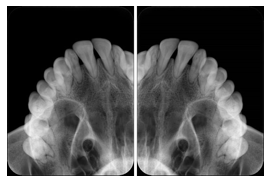

3. A patient in rural Minnesota experiences sudden vision loss and goes to a general ophthalmologist, who acquires OCT images and forwards them electronically along with a Structured Display to a retina specialist six travel hours away. The retina specialist is able to view the images in the standard layout that he is comfortable with, and to confirm that the patient has a choroidal neovascular membrane. He determines that is would be worthwhile for the patient to travel for treatment.

OCT Retinal Study with Cross Section and Navigation Structured Display

Figure OO-4. OCT Retinal Study with Cross Section and Navigation Structured Display